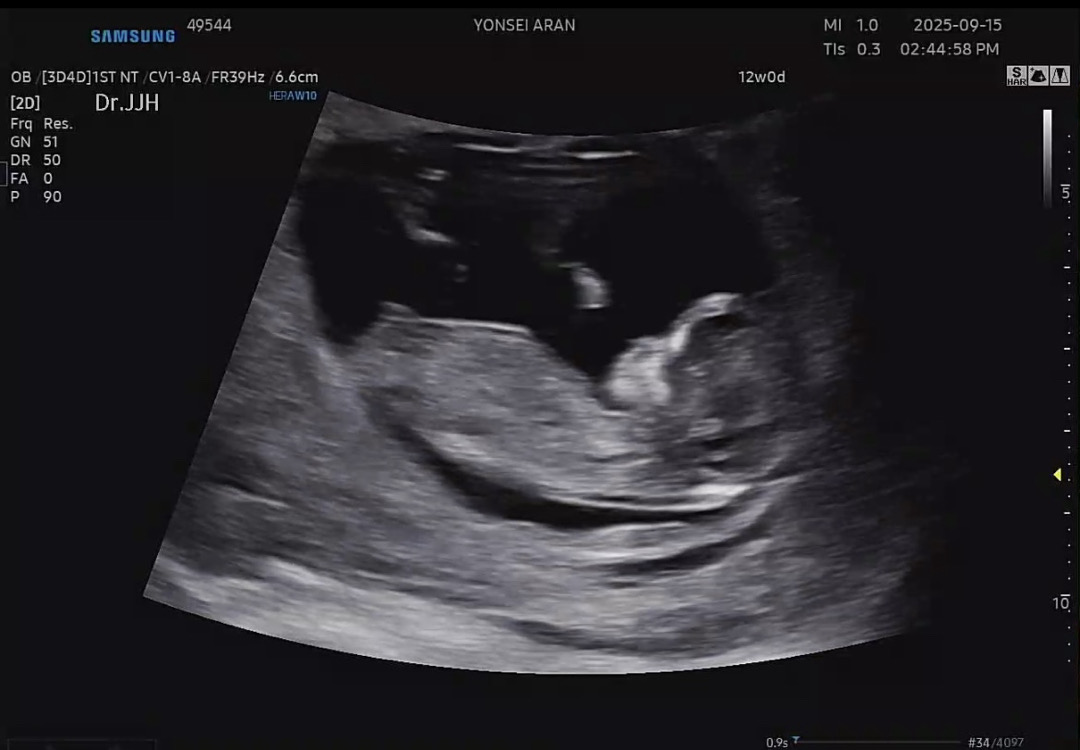

아들일까요??

뭔가 아들같은데 빌리AI에서는 아들이라고하고 네이버에서 찾아본 성별유추프로그램은 딸이라고하고 뭐가 맞을까요?ㅜㅜ 선생님이 사진 자세히보면 아실거에요~그랫는데 아무리봐도 모르겠어요😓